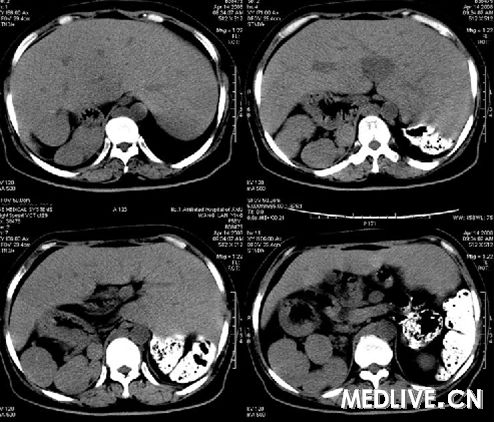

在一个风和日丽的午后,医院里进行了一次特殊的对比研究,研究的主角并非其他,而是两张截然不同的CT片,一张属于一个充满活力的年轻人,年仅25岁;另一张则是一位年近古稀的老人,已经度过了72个春秋,按照常理,这两者的身体状况应该有着天壤之别,令人惊讶的是,他们的CT片上的某些影像竟然如此相似。

我们先来探讨那位年轻的25岁患者,他正处于生命的黄金时期,身体各项功能应该处于巅峰状态,由于现代生活的压力与不良习惯,他的身体已经出现了一些隐患,虽然整体状况良好,但某些器官已经开始出现轻微的退化和炎症。

再来看那位72岁的老人,一般人认为,这个年龄的人身体应该出现了诸多衰老迹象,通过CT片,我们发现老人的身体某些部位虽然有些磨损,但整体结构却相当健康,他的骨骼密度、内脏功能以及血管状况都令人惊讶地保持得很好。

这两张CT片的相似性不仅仅体现在表面上的影像特征,更深层次地揭示了人类身体的复杂性和多样性,为什么一个年轻人的身体会出现老年化的迹象?而一个老年人的身体又能保持如此良好的状态?这背后究竟隐藏着怎样的原因?